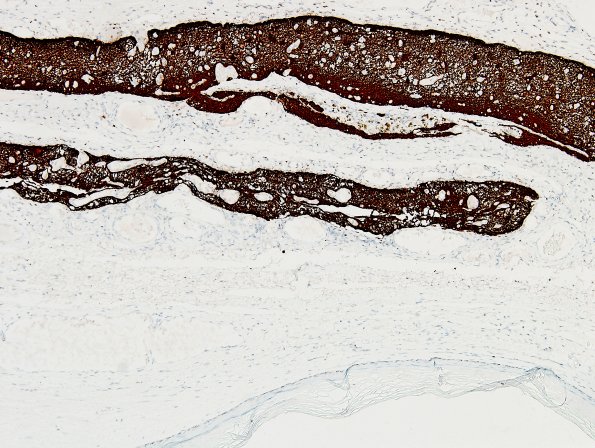

The glioneuronal tissue is highlighted by a glial fibrillary acidic protein (GFAP) immunostain, which also shows multiple nodules of glioneuronal heterotopia within the cyst wall. Patches of apparent flattened ependymal lining are also present. The extent of glial elements is well shown. (GFAP IHC)